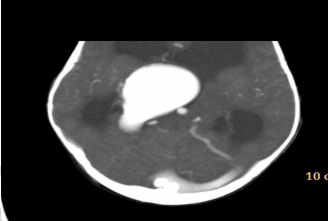

Um lactente de 3 meses de vida é encaminhado para atendimento em razão de aumento do perímetro cefálico (PC). A mãe não havia realizado pré-natal, mas nega uso de substâncias ou processos infecciosos durante a gestação. A criança foi encaminhada para avaliação cardiológica em razão de sopro cardíaco. Ao exame, percebe-se taquipneia leve, PC superior a 2 desvios-padrão, ausência de dismorfismos faciais e fontanela anterior aberta e abaulada. Tônus e trofismo estão preservados, e o paciente eleva os quatro membros contra a gravidade e tem reflexos normoativos. A tomografia de crânio é apresentada na figura. A respeito das informações apresentadas, qual é o diagnóstico para esse paciente?Provas

Disponível em: <http://www.radiopaedia.org/>. Acesso em: 20 maio 2018.